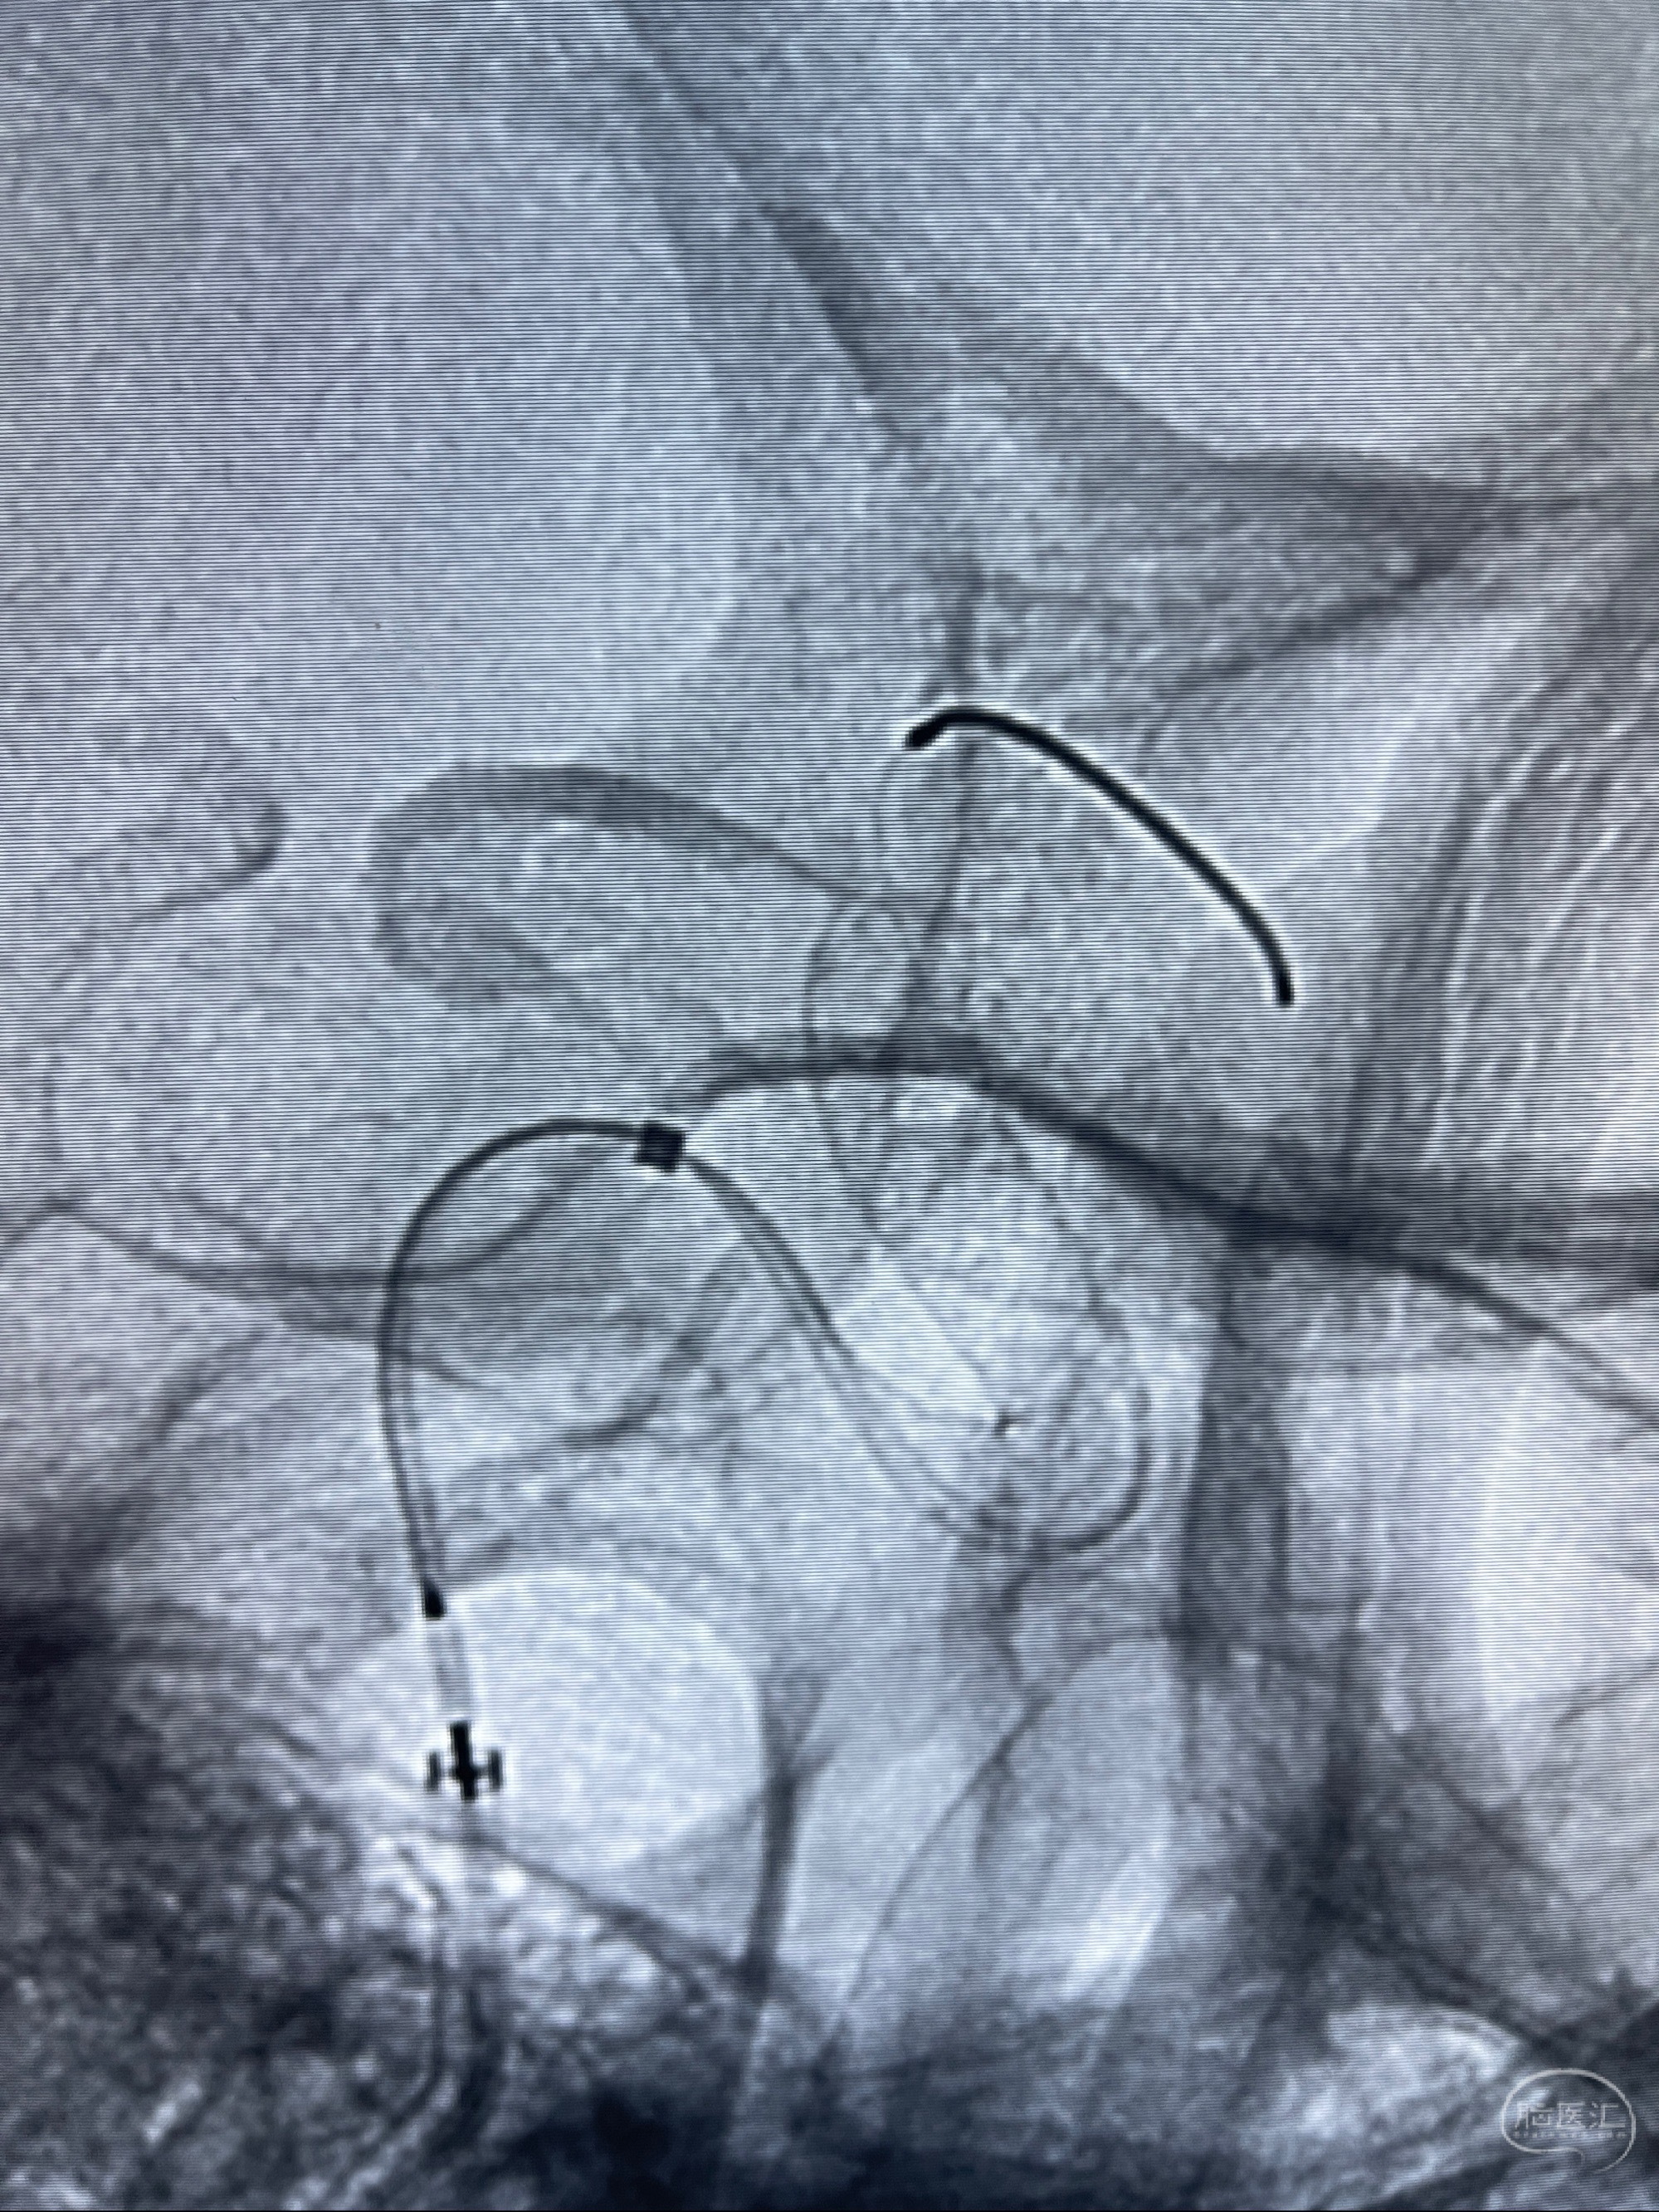

2023-07-27全脑血管造影:双侧颈内动脉眼动脉段动脉瘤,右侧较大

2023-08-01全麻下行双侧颈眼动脉瘤支架辅助栓塞

- pipeling4.5-20mm

- pipeline 4.0-20mm